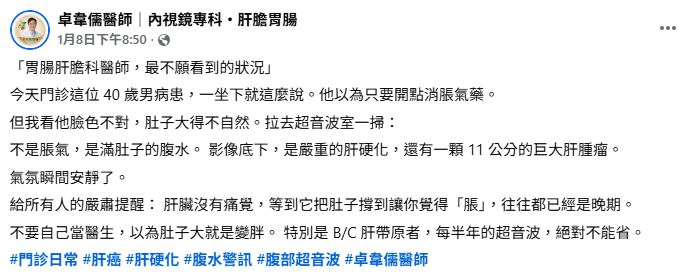

肝膽胃腸科醫師卓韋儒在粉專分享病例示警,一名40的男病患就診,原以為只是脹氣,拿點藥就好,但他見到對方「臉色不對、肚子大得不自然」,不僅皮膚灰暗呈土黃色、乾澀無光,眼白也偏黃,男子平躺後用手敲擊腹部還會聽見明顯聲響,翻身時也伴隨「水聲」。

卓韋儒醫師立刻驚覺不對勁,趕緊安排超音波檢查,影像出來後,在場所有人都瞬間安靜,因為男子根本不是脹氣,而是滿肚子的腹水,不僅有嚴重肝硬化,還有一顆11公分的巨大肝腫瘤。

卓韋儒醫師嚴肅提醒,「肝臟沒有痛覺,等到它把肚子撐到讓你覺得『脹』,往往都已經是晚期」,千萬別以為肚子大就是變胖,尤其是B、C肝帶原者,每半年的超音波追蹤檢查絕對不能省。